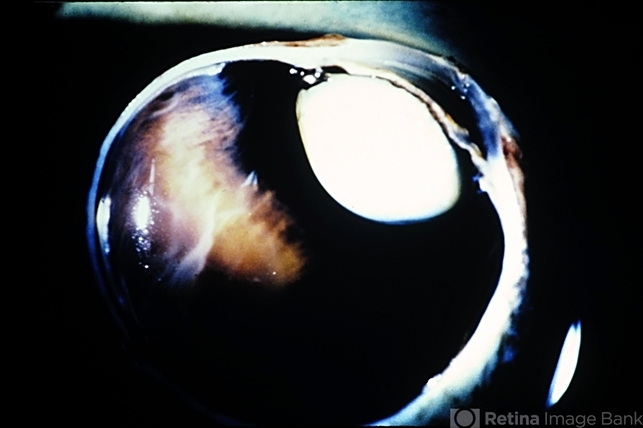

- angle-closure glaucoma interval, cataract

- Angle-closure glaucoma produced by pupillary block in an eye with an intumescent cataract. Gross appearance.